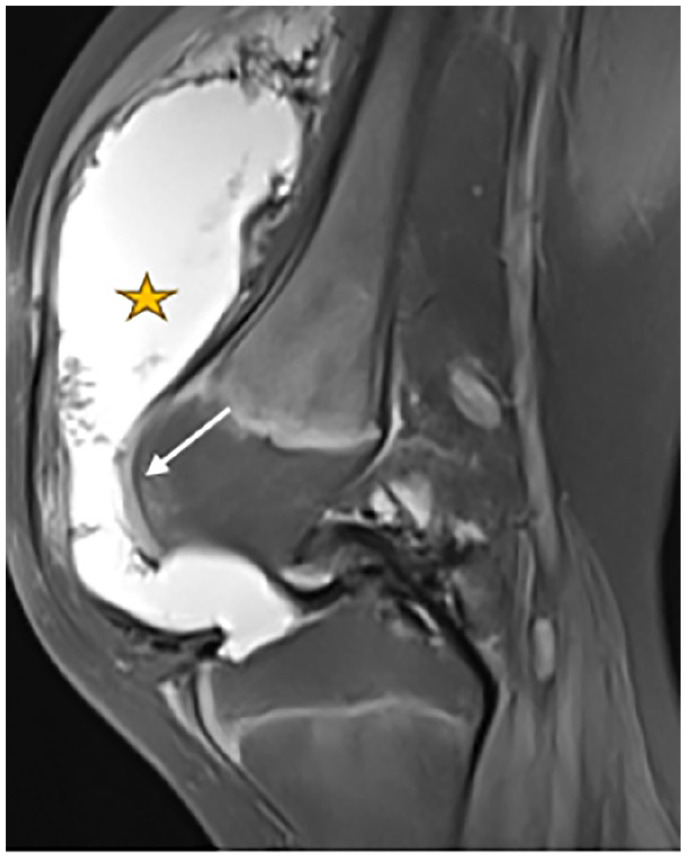

Hemophilia is a congenital coagulopathy characterized by a deficiency of coagulation factors and the development of haematomas and haemarthrosis, either spontaneously or after minor trauma. Recurrent joint hemorrhage in hemophilia patients leads to progressive and degenerative arthropathy, which affects around 90% of patients with severe disease and contributes significantly to disease morbidity. Positive diagnosis is based on biology. Imaging, particularly MRI, plays an essential role in assessing the evolution and complications, especially osteoarticular complications. We report 2 cases of severe hemophilia A, who presented with almost identical clinical and radiological symptoms. The patients developed severe arthropathy with a course marked by recurrences of haemarthrosis.

Abstract Image